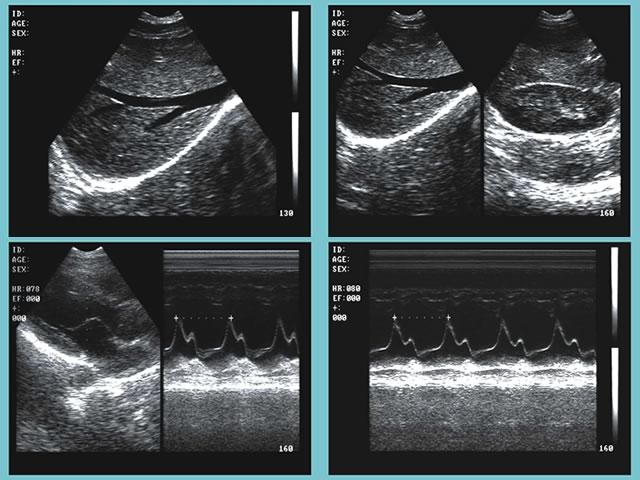

超聲診斷在醫(yī)學(xué)臨床上已使用多年。超聲波被廣泛使用,因為其易于使用且價格比其他成像方法便宜。一家大型美國診所在16個房間內(nèi)提供各種各樣的超聲波檢查。 Epiphan VGA Grid有助于超聲檢查人員在空中與相關(guān)專家進(jìn)行溝通

VGA Grid通過VGA圖像采集卡(Epiphan VGA2Ethernet)與安裝在每個檢查室中的最頂尖的超聲波設(shè)備相連接。VGA圖像采集卡捕捉來自設(shè)備的信號,并通過以太網(wǎng)發(fā)送至VGA Grid。它可以同時捕捉和記錄帶有時間戳的所有會話。進(jìn)行檢查的超聲醫(yī)師在其得出結(jié)論前,可能需要與專家進(jìn)行討論。完成成像后,檢查室專家可能有問題需要與主治醫(yī)生、主管或其他受過專業(yè)醫(yī)療成像培訓(xùn)的專家進(jìn)行討論。

超聲視頻可以在需要時進(jìn)行重放或縮小。無論專家們在哪里,他們都能夠查看來自多個來源的視頻。他們通過網(wǎng)絡(luò)接口訪問超聲波圖像(錄制或直播)。根據(jù)研究結(jié)果,他們判斷進(jìn)一步的研究是否會有幫助,然后做報告,并告知病人結(jié)果。 VGA Grid使一次性查看來自多個檢查室的超聲設(shè)備信息成為可能,中央控制中心就能監(jiān)測到哪間房間是可用的。高端的設(shè)備可以使門診超聲檢查師立即獲得診斷信息,更有效地治療患者。